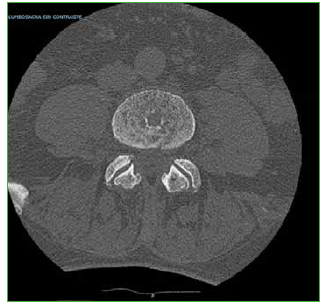

Symptomatic intraosseous Schmörl herniation